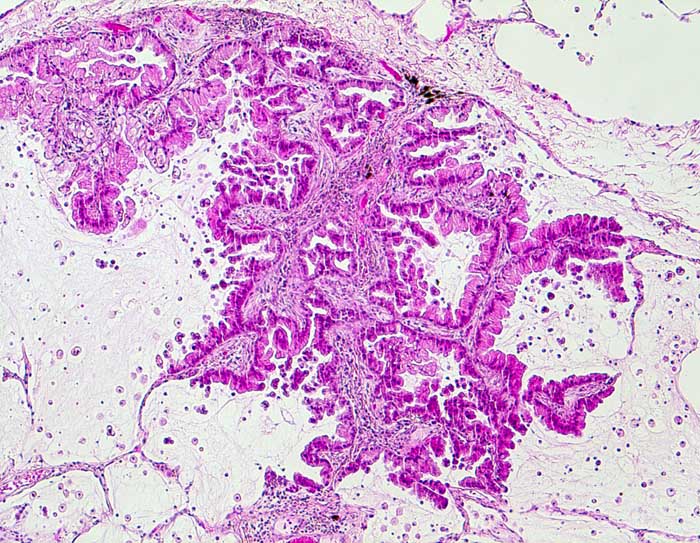

PathoPic – image database / PathoPic ID 6574 - muzinöses Adenokarzinom der Lunge

muzinöses Adenokarzinom der Lunge

Monomorphe, hochzylindrische schleimbildende Zellen mit basalständigen Kernen und geringen Atypien tapezieren die Alveolarsepten aus. Das Lungengerüst bleibt erhalten. Die Alveolarlichtungen sind schleimgefüllt und enthalten Schaumzellen.